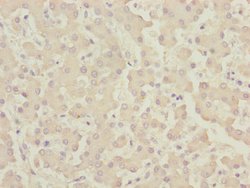

CENPK Polyclonal Antibody for Western Blot, IHC (P), ELISA

| ELISA, Immunohistochemistry (Paraffin), Western Blot | |